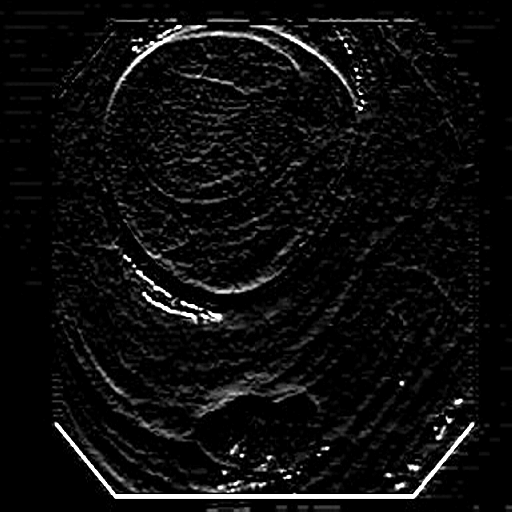

3.3 Edge-Guided Feature Enrichment Unit

The scarcity of annotated data in clinical practice hinders existing methods’ ability to capture polyp boundaries accurately. To address this, we propose the Edge-Guided Feature Enrichment (EGFE) unit, designed to enhance boundary quality in segmentation masks. EGFE robustly preserves edge information, mitigating the issue of weak boundaries, bridges the semantic gap between low-level and high-level features, and directly captures spatial features of polyps from input images. A pre-processing step incorporating a 2D Sobel operator [32] ensures the preservation of crucial edge details during convolutions.

The Edge-Guided Feature Enrichment (EGFE) unit actively enhances feature representation by integrating edge knowledge into the set of features. It applies a Sobel operator to the input feature set, generating separate gradient magnitude maps for horizontal and vertical directions (Fig. 3). As illustrated in Fig. 3, the Sobel operation in a single direction captures limited information about the polyp. However, combining these maps (Fig. 3(d) and Fig. 3(h)) effectively captures polyp boundaries and enriches learned features. The final gradient magnitude map, produced using the Euclidean norm (Eq. 1), highlights regions with significant intensity changes at polyp boundaries.